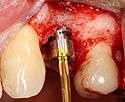

An incision is made across the area and the flap of gingiva is opened to show the bone of the jaw.

An incision is made across the gingiva, and the flap of tissue is reflected to show the bone of the jaw.

A series of slow-speed drills create and gradually enlarge a site in the jaw for the implant to be placed. The hole is called an osteotomy.

Once the bone is exposed, a series of drills create and gradually enlarge a site (called an osteotomy) for the implant to be placed.

The implant fixture is turned into the osteotomy. Ideally, it is completely covered by bone and has no movement within the bone.